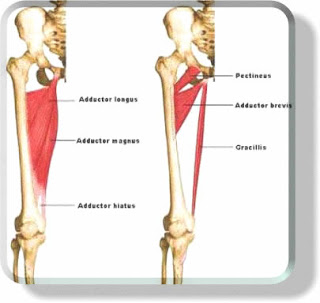

- The dynamic stabilisers of the knee are all the muscles and their aponeuroses, including:

- Quadriceps

- Pes Anserinus

- Popliteus

- Hamstrings